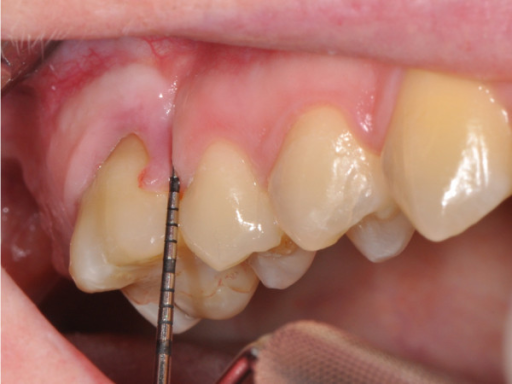

Descripción: Clinical examination revealed 7-mm probing depths, circumferentially around a mandibular implant, bleeding on probing, and the presence of exudate and gingival inflammatory edema